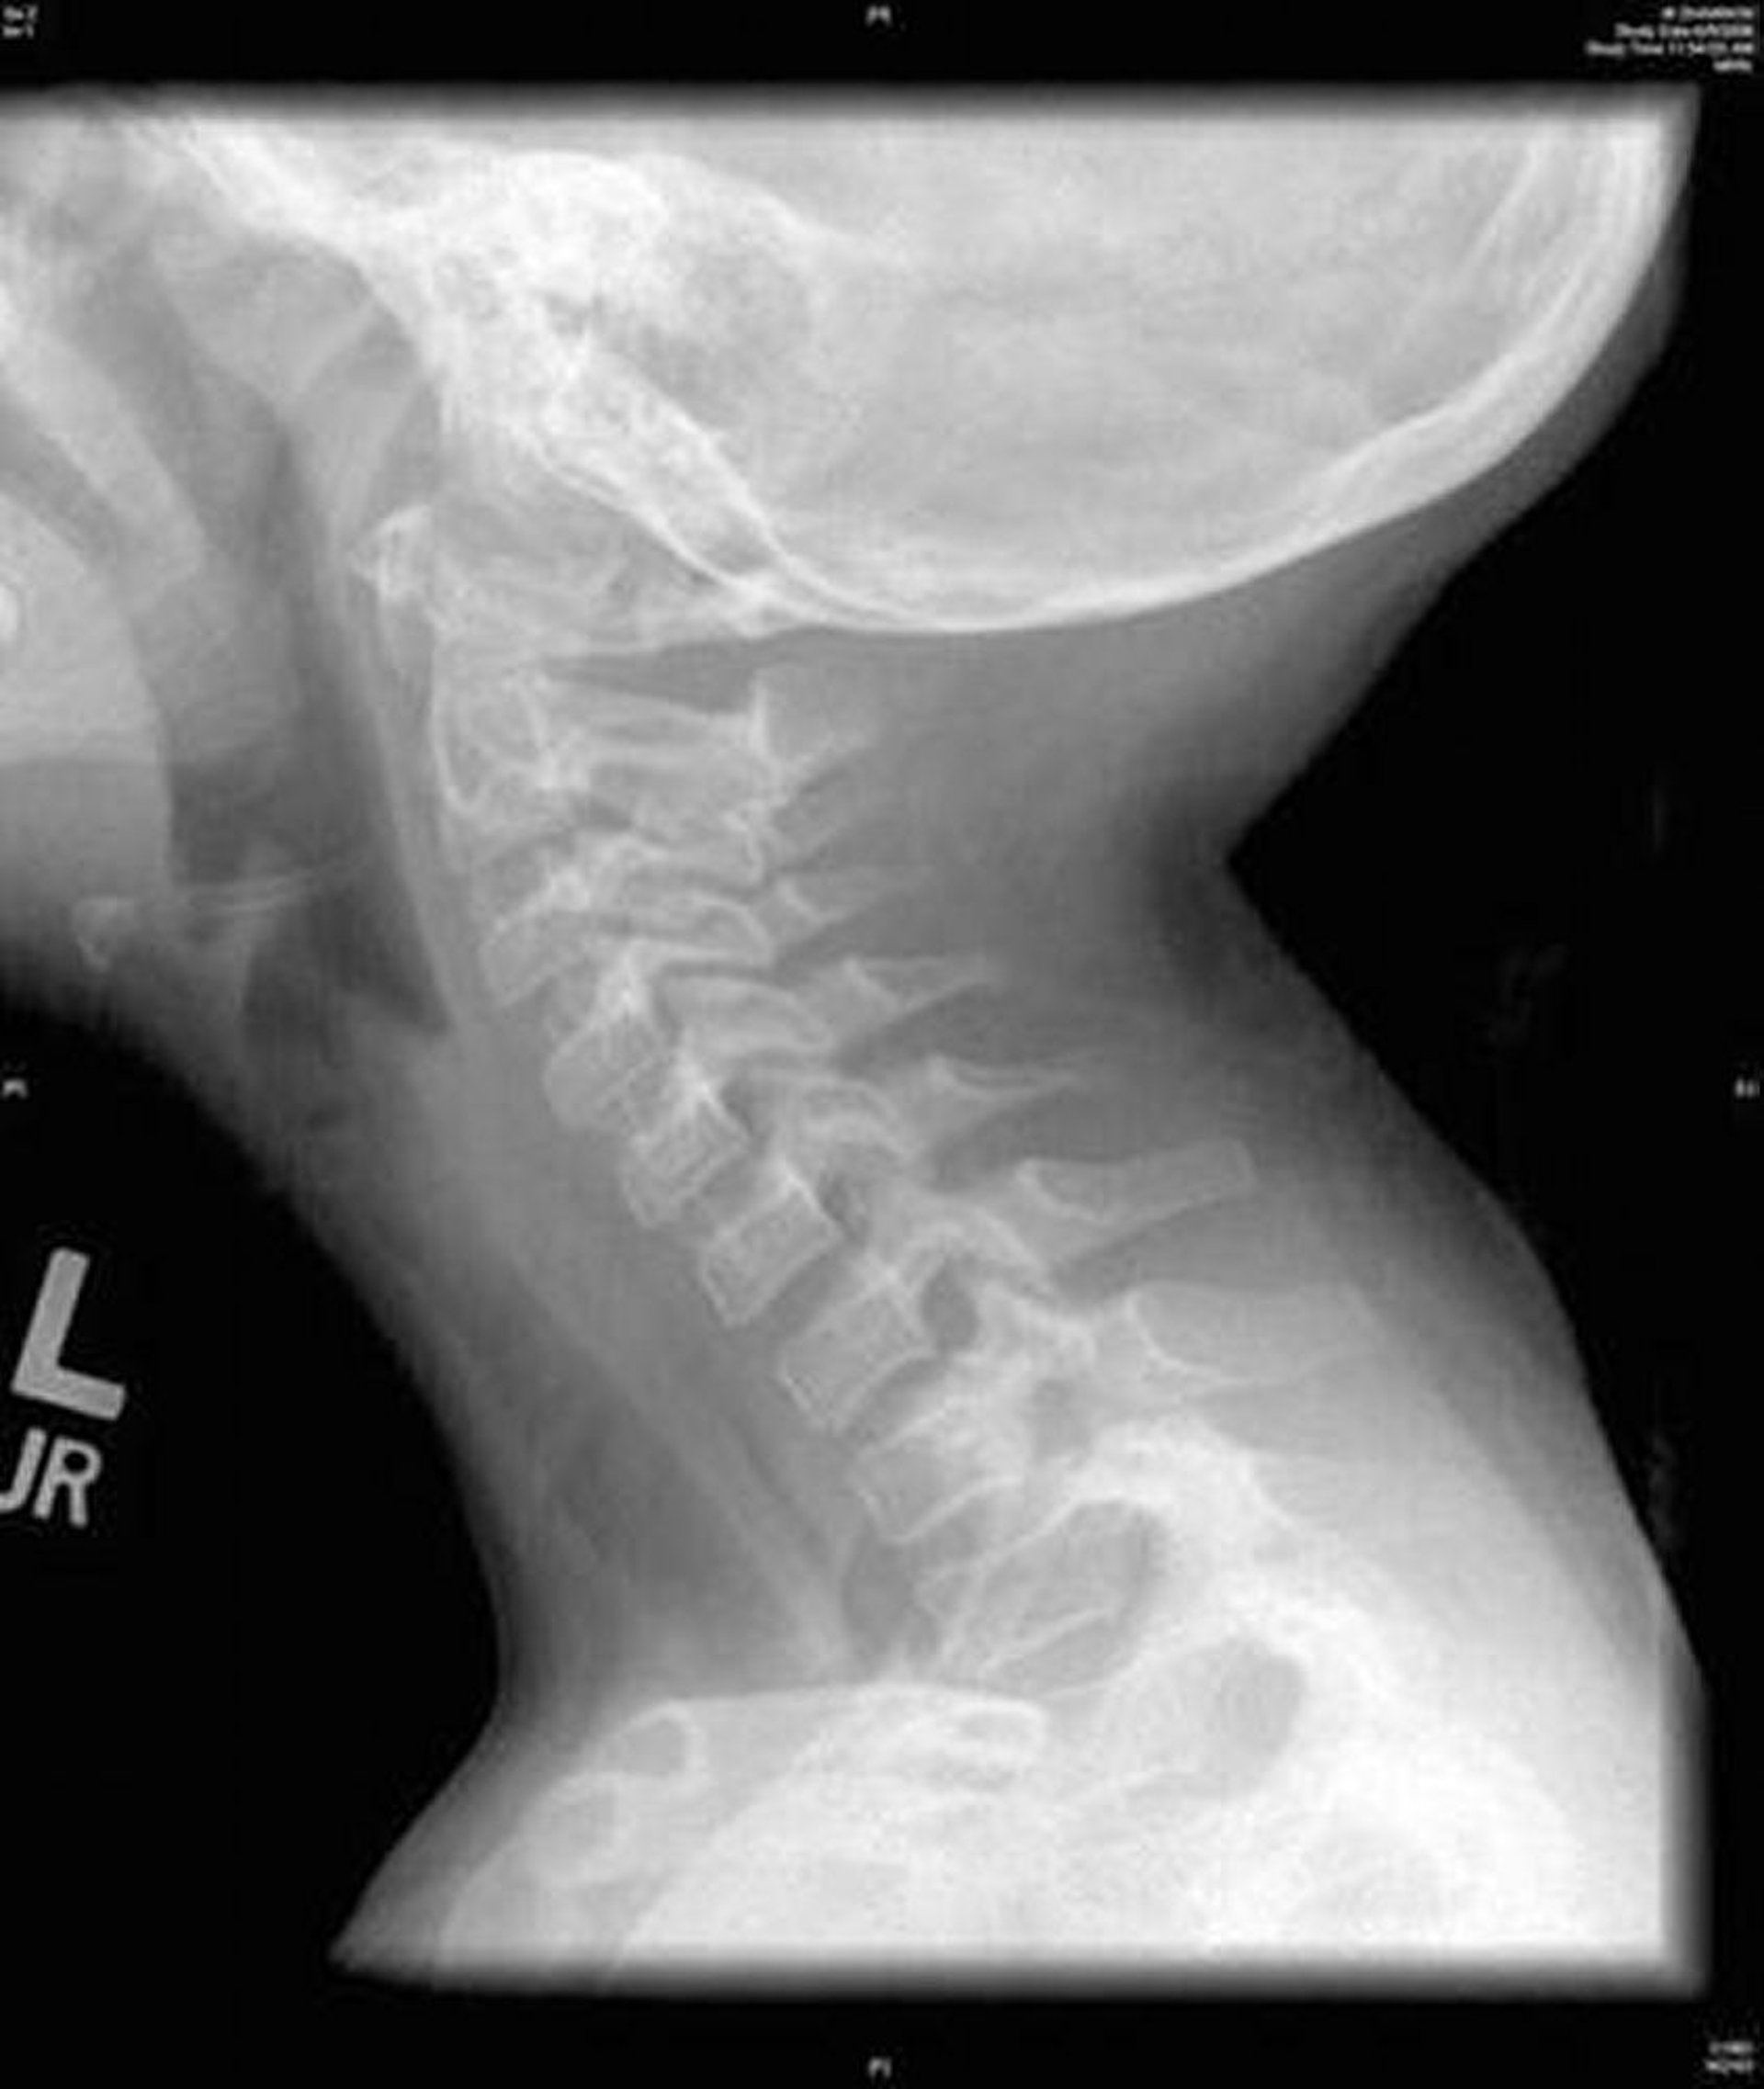

Bakterielle Tracheitis (Röntgenbild)

Diese Abbildung zeigt eine seitliche Röntgenaufnahme des Halses, die eine diffuse Unregelmäßigkeit der Luftröhre aufweist, die für eine bakterielle Tracheitis charakteristisch ist.